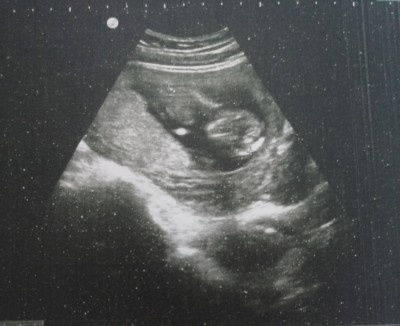

Merhaba Güzel Teyzeleri ilk gebeliğim 12 3 ultrason görüntüsü cinsiyet tahmini alabilir miyim son âdet tarihi 13 Ağustos

Erkek gibi geldi  bana  sağlıkla al kucağına

Hiç anlamam ama nedense kız gibi geldi bana